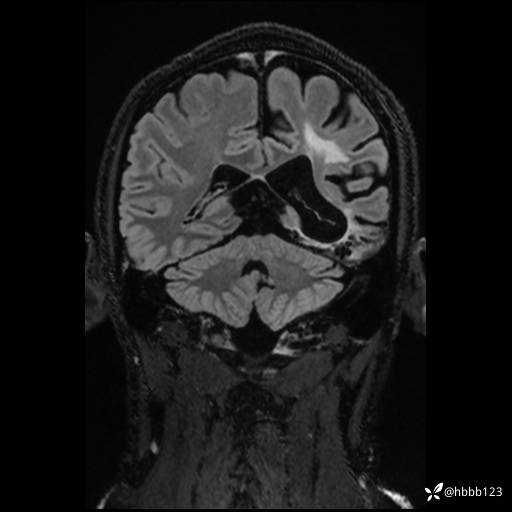

CUBE FLAIR冠状位: